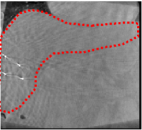

An example of CT/CBCT and MR/CBCT registration results are shown in figures 3 and 4, respectively. For both cases, the CBCT image (first column) was acquired intra-operatively after needle insertions and was employed as a reference for image registration. The pre-operative image is displayed before registration (second column), after PM-EA (third column) and after PM-EA+Evo (fourth column). The occurrence of patch shifts is reported for each spatial direction in panels (m–o): for each histogram, the shift with maximal occurrence is shown by the red dashed line. For panels (a–l), a ROI — manually defined on the CBCT image/encompassing the liver — is shown using red dash lines. Our visualization shows an improved correspondence of the contour of the liver with the manually defined liver boundary when the PM-EA solution is employed (see 3(c,g,k) and 4(c,g,k)). Moreover, an even better correspondence of the contour is observable using the PM-EA+Evo solution (see 3(d,h,l) and 4(d,h,l)).

Trans.

[X-Y]

CBCT

(a)

MRI / No registration

(b)

MRI / PM-EA

(c)

MRI / PM-EA+Evo

(d)

Sag.

[X-Z]

(e)

(f)

(g)

(h)

Cor.

[Y-Z]

(i)

(j)

(k)

(l)

(m)

(n)

(o)